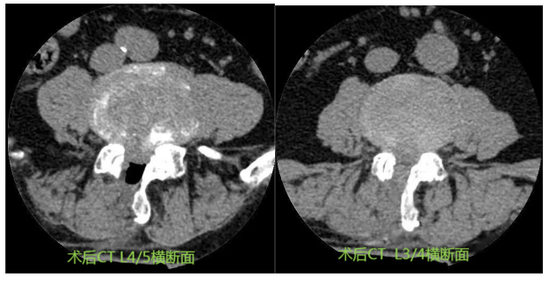

“终于能挺直腰板走路了!”今年6月,李女士(化名)通过单侧双通道内镜(UBE)手术,顺利摆脱腰腿疼痛。日前复诊时,患者李女士(化名)开心地表示自己已恢复日常工作。据她描述,平时但凡坐得时间长一点,或坐姿、睡姿稍显随意,整个后腰就会“闹脾气”,连带着左下肢都会出现放射性疼痛,即使卧床休息都无法缓解。“在其他医院检查后,医生说是腰椎间盘突出,巨大髓核压迫神经根,这才导致了剧烈疼痛和肢体无力、麻木。”为了彻底摆脱疼痛困扰,李女士尝试了许多方法,可症状非但没有缓解,反而“愈演愈烈”。

来到德州市第二人民医院骨科后,骨科医疗组长姜小坤结合李女士的具体情况,综合考虑之后,建议她进行单侧双通道内镜(UBE)手术。“这种手术就像‘开锁’一样,我们首先会通过影像检查精确定位,找到‘锁孔’的位置并进行标记,然后再精准创建两个像‘钥匙孔’般大小的切口,在脊柱内镜的辅助下将病变的颈椎间盘精准摘除,解除神经压迫,即为成功‘开锁’。”姜小坤一番生动形象的讲解,让李女士重新燃起了治愈的希望。

术后效果立竿见影。当天,李女士惊喜地发现,曾让自己痛苦不堪的不适症状得到了显著缓解;术后第二天,李女士便能在医护人员的指导下下床活动。经过术后一周的观察与护理,李女士顺利出院。